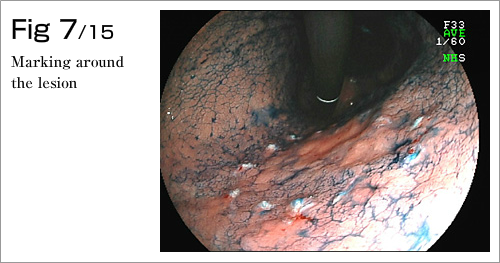

The procedure is done in several steps. First, the margins of the lesion are marked by electrocautery, and then a submucosal injection is used to lift the lesion (Diagram 4-8). After which, a circumferential incision into the submucosa is made around the lesion (Diagram 9). Finally, the lesion is dissected from underlying deep layers of GI tract wall with electrocautery knife and removed (Diagram 10-13). The lesion, mainly existing in the mucosal layer (1st layer), can be completely excised along with the submucosa (2nd layer)(Diagram 14-15).